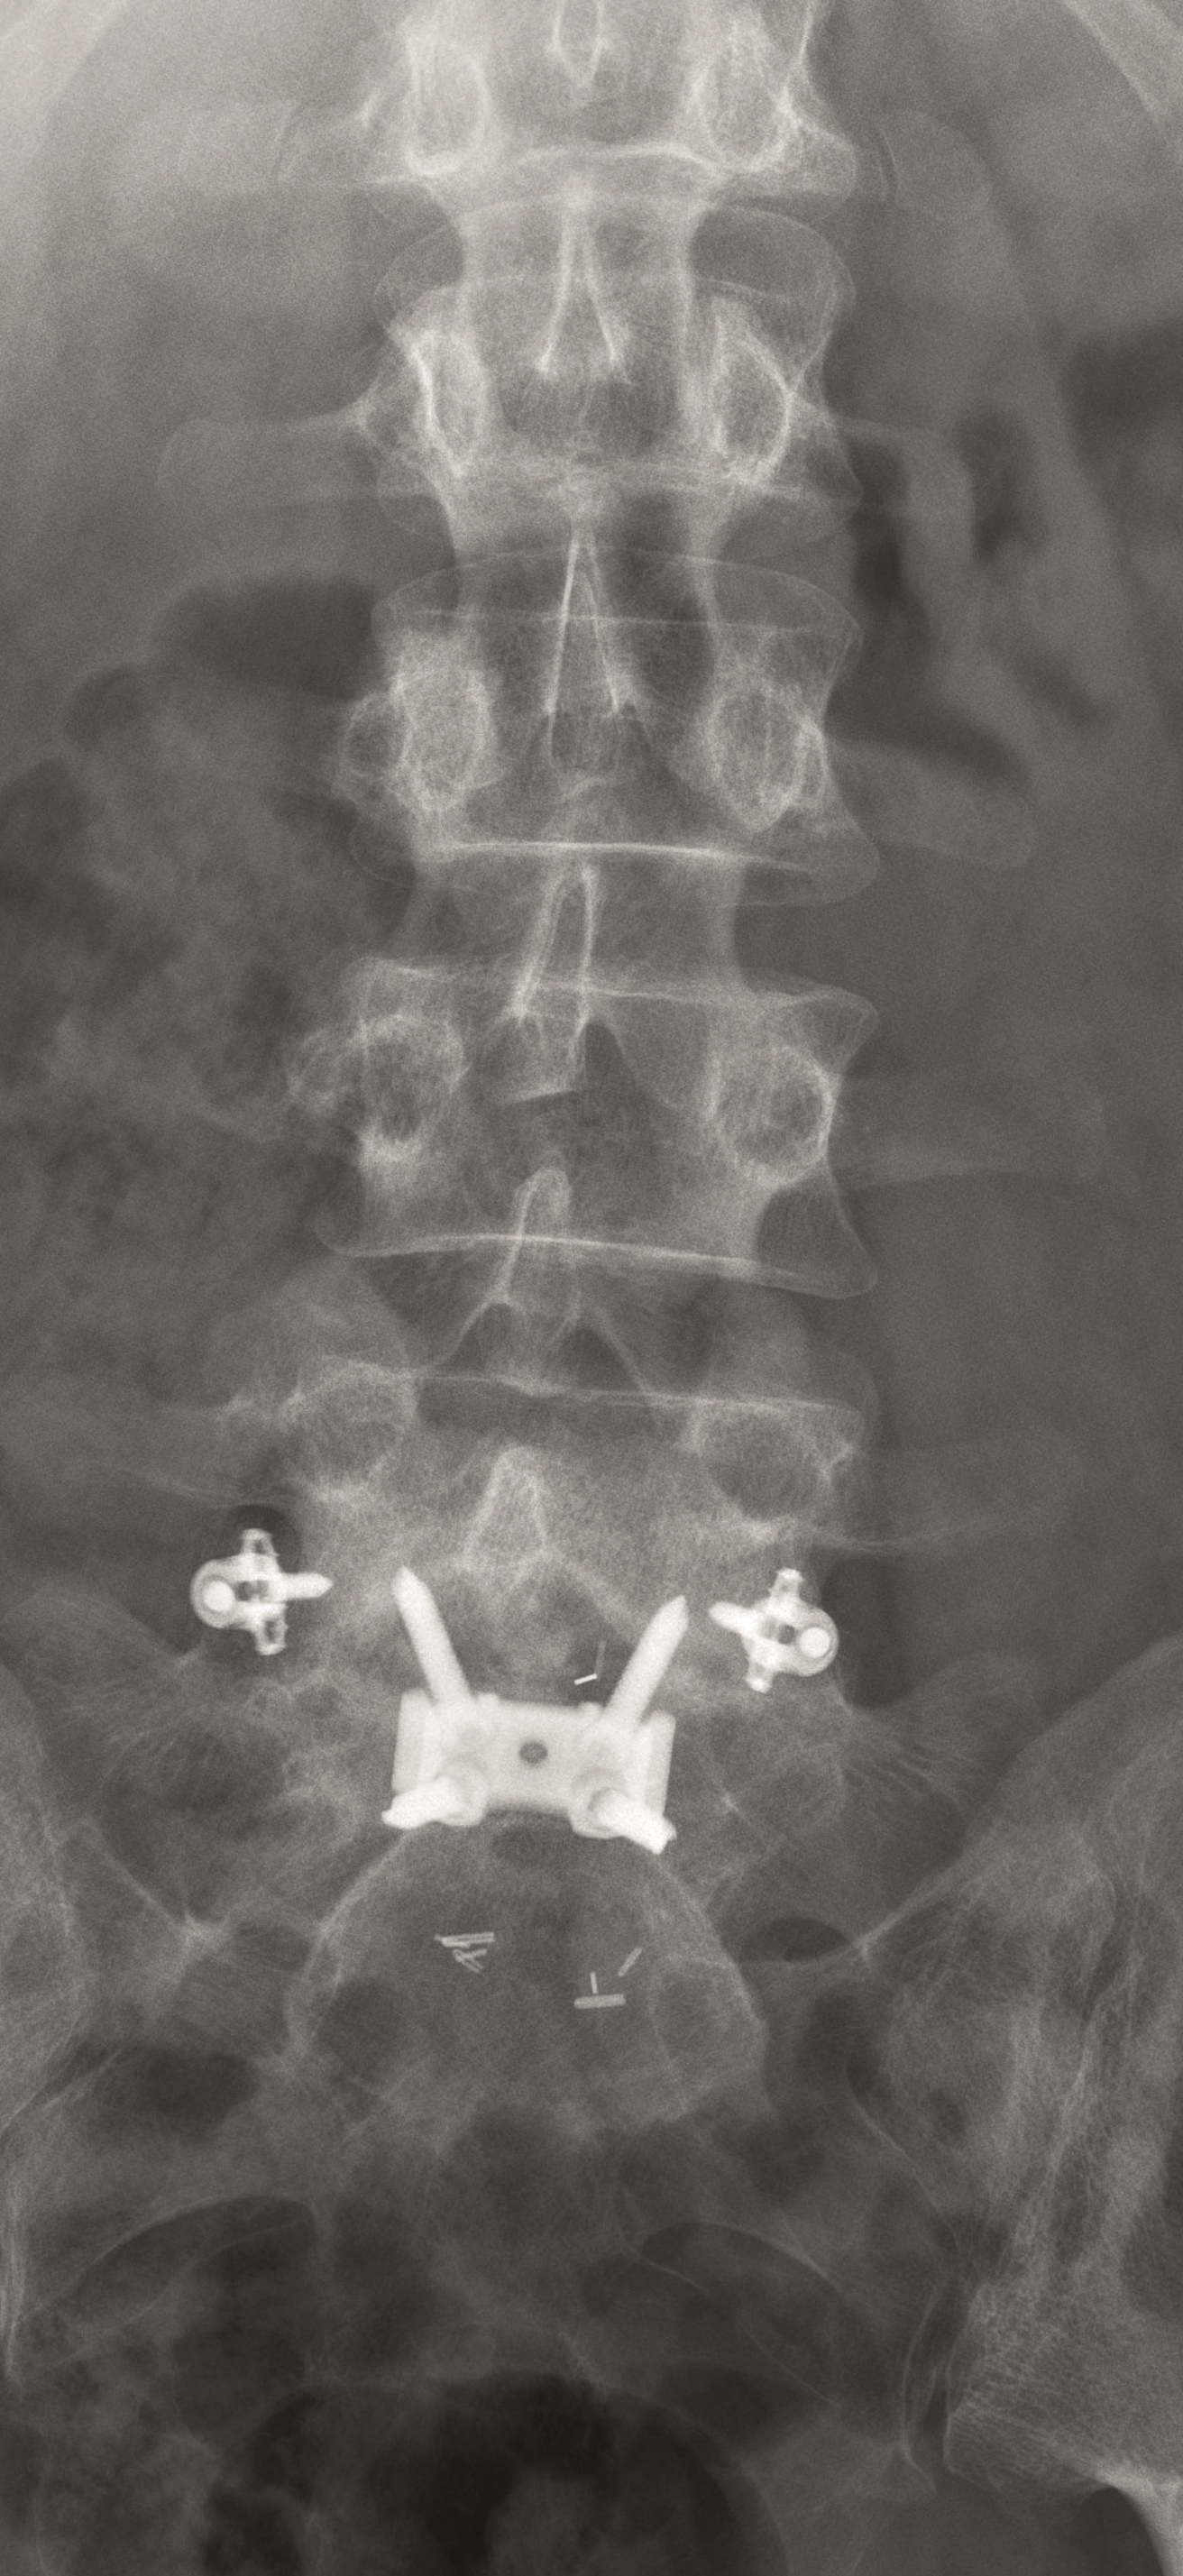

Case 5 : Degenerative scoliosis

A female patient 66-years-old with back pain, leg pain, and degenerative deformity. The x-rays show left convex degenerative scoliosis Cobb T12-L3 38. Nonoperative treatment failed. Treatment option was posterior fusion T11-L5, with URS Facet Wedge L2-L3 unilaterally.

A conventional approach for posterior correction was taken, with indirect Foraminal decompression and Facet Wedge fusion (apex curve). Facet Wedge introduction after curve correction with rod in situ. X-ray follow-up initially (Fig 20), with CT assessment of Facet Wedge fusion after 6 months (Fig 21).